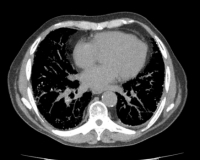

- КТ легких. Компьютерная томография служит стандартным методом выявления оссификации и сопутствующих заболеваний легких. На КТ определяются круглые узелки или ветвящийся древовидный рисунок. С помощью рентгенографии легких могут быть обнаружены диффузные изменения в легких, однако исследование не позволяет судить об их происхождении.